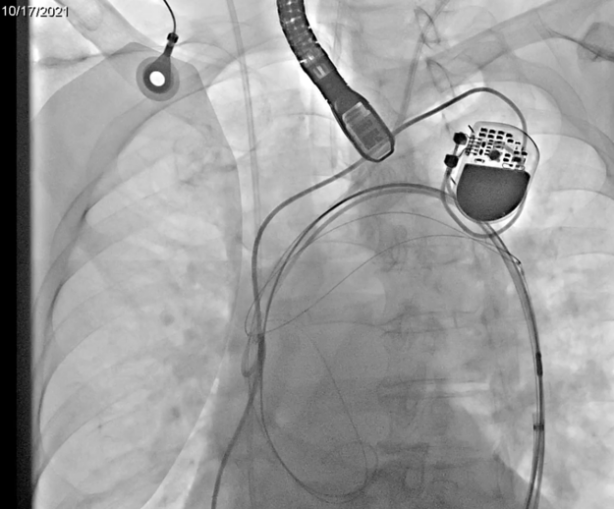

患者为女性,85岁,2013年行冠脉支架植入术,2018年再次行冠脉支架植入术合并房颤冷冻球囊消融术,2020年行永久起搏器植入术。1年前无明显诱因出现间断活动后气促,活动耐力下降,近3月上述症状加重。术前CT显示主动脉瓣为三叶瓣,重度钙化,术前经胸超声主动脉瓣口峰值流速5.7m/s,峰值压差124mmHg,平均跨瓣压差78mmHg,诊断为主动脉瓣重度狭窄伴关闭不全。

在利用Leaflex™ Performer器械从多角度进行自体主瓣修复过程中,患者血流动力学保持稳定,该过程无需在起搏的条件下进行操作,完成修复后主动脉瓣反流未加重。TEE测得患者瓣口峰值流速降低37.4%,峰值压差降低58.9%,平均压差降低56.4%。修复完成后,顺利撤回Leaflex™ Performer器械。患者术后恢复良好,于2021年10月27日出院。